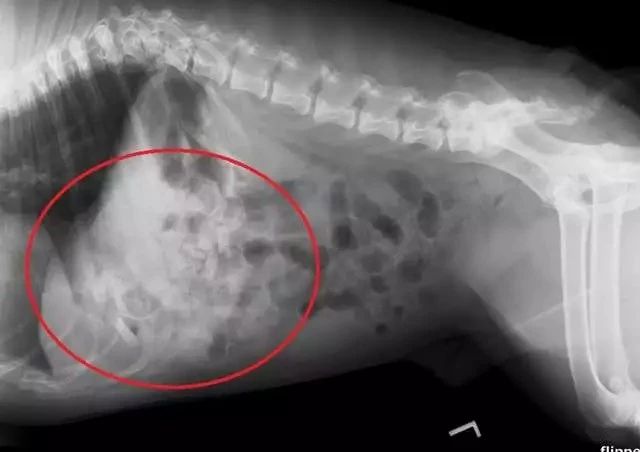

在X光照射下才终于查明病因,狗狗胃中塞满了异物。

医生立即安排了手术,结果让人大吃一惊:竟从狗子的胃里取出了19个安抚奶嘴。主人从来没有注意到安抚奶嘴居然被狗狗偷吃了这么多。

偷吃戒指、偷吃奶嘴还不是最厉害的。你能想象这只狗一共吞下了109颗石子吗!